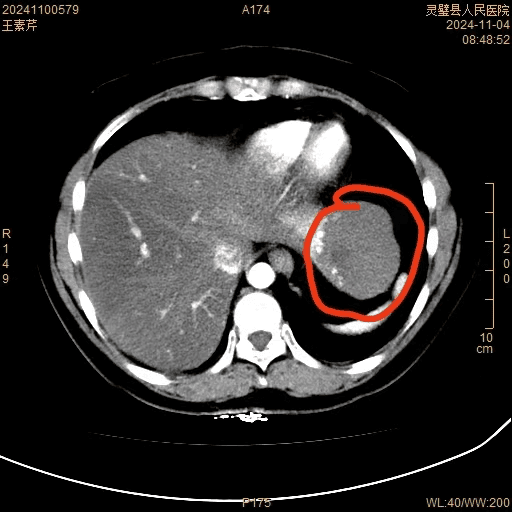

患者53岁,腹胀伴恶心20余年,一直保守治疗。2天前于外院体检时发现左隔下脾胃前上间隙内团块软组织密度影,与肝左叶分界不清。患者及其家属至我院普外三科寻求进一步治疗。

普外三科汤军主任结合患者病史、查体以及CT等检查,初步诊断为“肝血管瘤”,拟用微创手术方式治疗。

经过患者和家属同意,完善术前准备后,在曹葆强院长的指导下,普外三科团队在麻醉科及手术室的共同配合下,成功开展首例腹腔镜下左肝叶切除术,在不损伤右侧肝叶的情况下,切除直径近7cm大血管瘤。术中可见肝血管瘤与左侧膈肌黏连,腔镜下完整剥离瘤体,手术顺利,出血少,术后病人恢复快,第二天即下床自主活动。